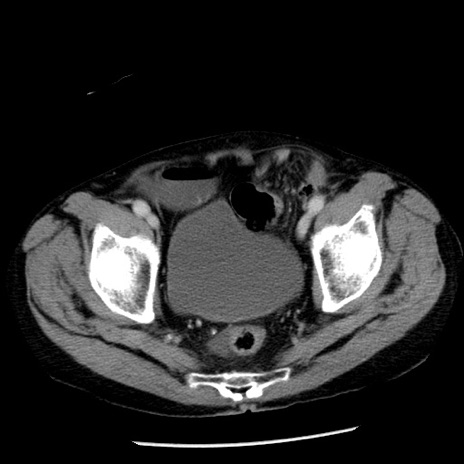

症例26(横断像)

【症例】80歳代男性

【主訴】嘔吐

【現病歴】昨晩2回嘔吐あり、今朝になっても嘔吐あり。来院。

【既往歴】胃潰瘍

【身体所見】意識清明、BT 37.6℃、BP 166/95mmHg、HR 100bpm、SpO2 97%、腹部:平坦・軟、腸蠕動音聴取良好、圧痛なし。

【データ】WBC 21900、CRP 1.46